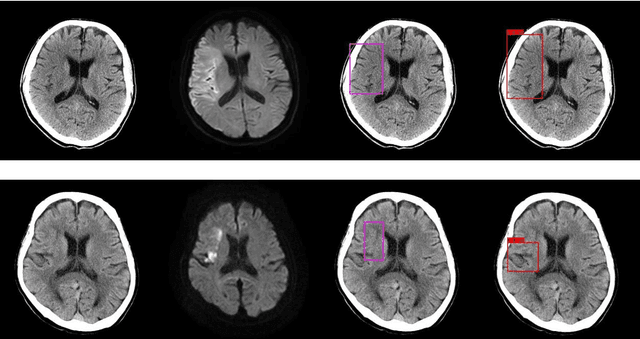

Abstract:Background and Purpose: We aimed to develop and evaluate an automatic acute ischemic stroke-related (AIS) detection system involving a two-stage deep learning model. Methods: We included 238 cases from two different institutions. AIS-related findings were annotated on each of the 238 sets of head CT images by referring to head magnetic resonance imaging (MRI) images in which an MRI examination was performed within 24 h following the CT scan. These 238 annotated cases were divided into a training set including 189 cases and test set including 49 cases. Subsequently, a two-stage deep learning detection model was constructed from the training set using the You Only Look Once v3 model and Visual Geometry Group 16 classification model. Then, the two-stage model performed the AIS detection process in the test set. To assess the detection model's results, a board-certified radiologist also evaluated the test set head CT images with and without the aid of the detection model. The sensitivity of AIS detection and number of false positives were calculated for the evaluation of the test set detection results. The sensitivity of the radiologist with and without the software detection results was compared using the McNemar test. A p-value of less than 0.05 was considered statistically significant. Results: For the two-stage model and radiologist without and with the use of the software results, the sensitivity was 37.3%, 33.3%, and 41.3%, respectively, and the number of false positives per one case was 1.265, 0.327, and 0.388, respectively. On using the two-stage detection model's results, the board-certified radiologist's detection sensitivity significantly improved (p-value = 0.0313). Conclusions: Our detection system involving the two-stage deep learning model significantly improved the radiologist's sensitivity in AIS detection.